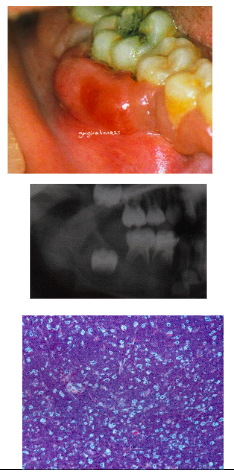

ORAL:

*Mucosal pallor

*Mucosal petechiae, purpura

*Ulcerations

*Fungal infections (eg candidiasis)

*Viral Infections (eg herpetic lesions)

*Gingival Leukemic Infiltrate = tumor-like collection of leukemic cells (granulocytic sarcoma or extramedullary myeloid leukemia, old term = chloroma), usually myeloid, type, spontaneous bleeding (no spontaneous bleeding in benign hyperplasia)

Non-Hodgkin’s Lymphoma clinical features

*Most common presentation: painless, persistent enlargement of lymph nodes

*Extra nodal disease can occur → mainly presents in soft tissue

*Enlarged tonsil, painless palatal swelling, or gingival mass (may mimic inflammatory disease)

*Tumor isnontender, diffuse, boggy, discolored swelling (+/- ulcerated)

*Rarely can occur in jaw bones